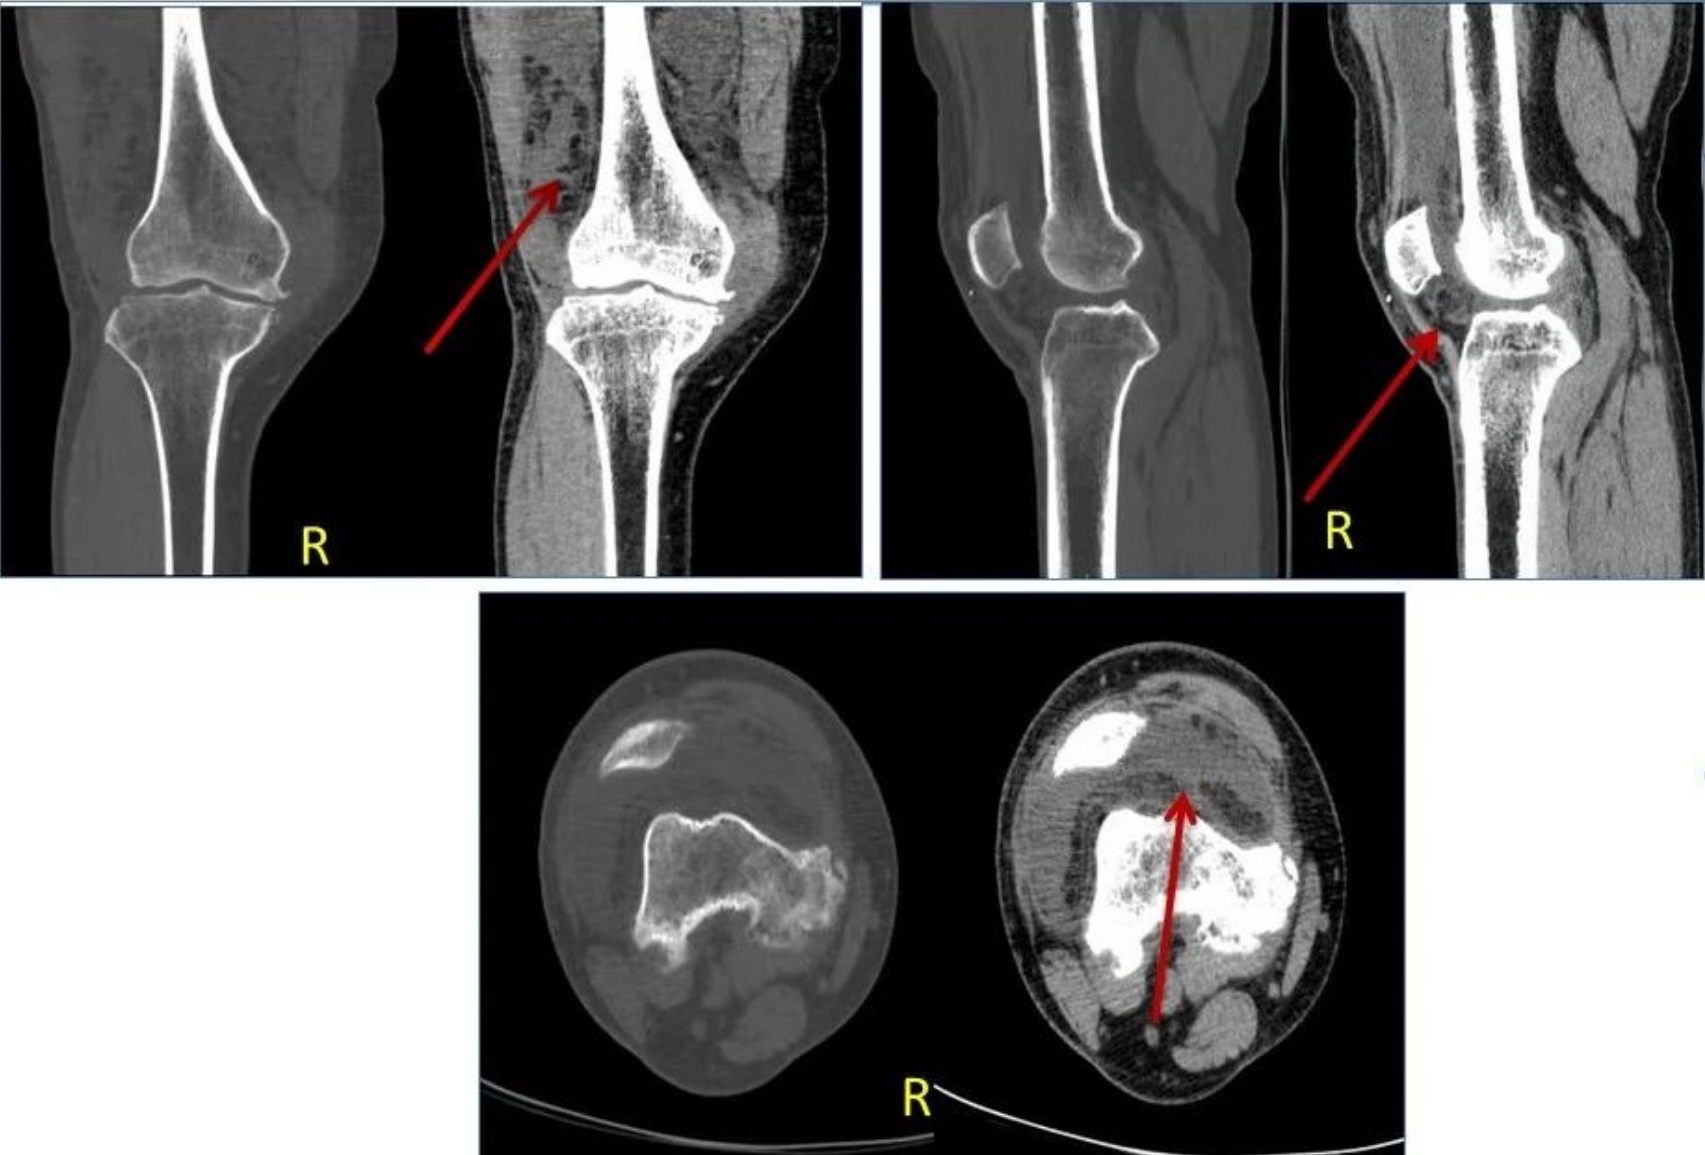

2、CT可见髌上囊内树枝状、绒毛状的脂肪密度影,临近骨质可有吸收及骨质增生硬化等改变,多合并关节腔积液。

2、滑膜软骨瘤病。滑膜软骨瘤病为关节滑膜非肿瘤性化生,导致滑膜增厚,以关节腔内多发软骨结节为特征。影像学表现取决于骨化程度以及是否存在软骨样基质。X线及CT可见钙化或骨化的关节游离体。对于少数无钙化或骨化的病灶,T1、T2表现为中等信号,结节边缘可呈低信号,钙化或骨化的游离体T1、T2均呈低信号或T1呈高信号,T2呈中等高信号,增厚的滑膜T1为等、低信号,T2为稍高信号。滑膜软骨瘤病与滑膜树枝状脂肪瘤的鉴别点在于前者平片及CT可以看到关节游离体,而后者无此改变,另外病变多无后者弥漫且具有特征性的形态。

上图,滑膜软骨瘤病。X线可见胫骨前缘钙化结节,MR显示髌下深囊的钙化结节在PDWI不压脂序列上呈低信号。